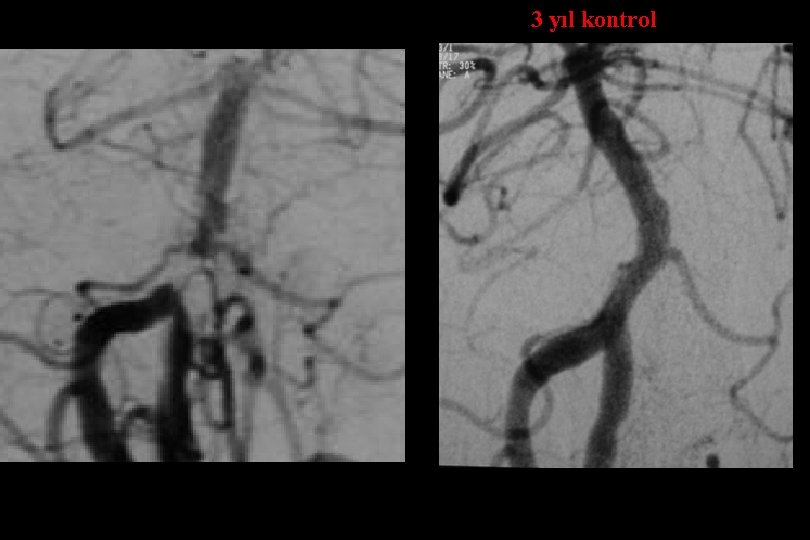

3 yıl kontrol